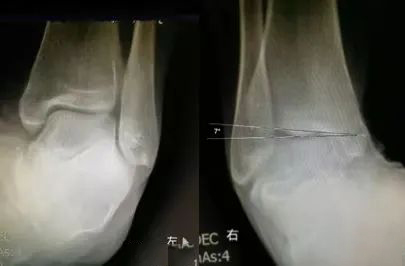

生活中,崴脚后常常忽视外固定的作用,特别是未存在撕脱骨折以及 X 线片假阳性者,踝关节应力位 X 片对于单纯的韧带损伤可发现踝关节不稳。

距骨倾斜角:内翻应力正位片中距骨相对于胫骨远端关节面倾斜角度 ≥ 9°,即可考虑踝关节不稳,但此时应考虑患者的职业,如芭蕾舞演员可存在足踝部韧带松弛

28 岁青年女性,约 2 年前左踝首次发生崴脚,未行外固定处理,近 1 年来左踝间断多次崴脚,双侧踝关节应力正位片测量距骨倾斜角,左侧为 10°,右侧 4°,左侧应力位状态下感疼痛,右侧无不适感,考虑左侧踝关节不稳。

30 岁青年女性,1 年前右踝首次发生崴脚,未行外固定,伤后右踝间断数次崴脚,双侧踝关节应力正位片测量距骨倾斜角,左侧为 0°,右侧 7°,右侧虽尚不能诊断踝关节不稳,但距骨倾斜角增大,对比对侧仍考虑为崴脚后未外固定所致。